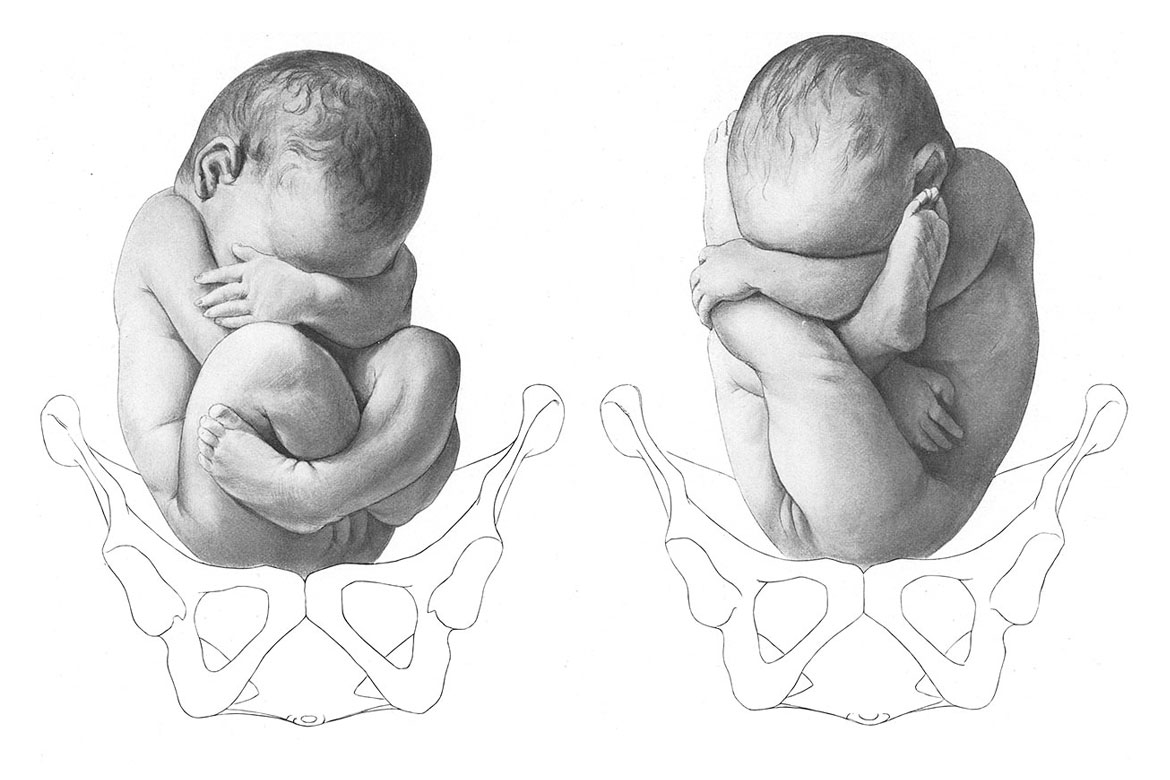

1 Позиция задний вид затылочного предлежания

1 Позиция передний вид затылочного предлежания

Задний вид затылочного предлежания биомеханизм родов

Биомеханизм родов в переднеголовном предлежании